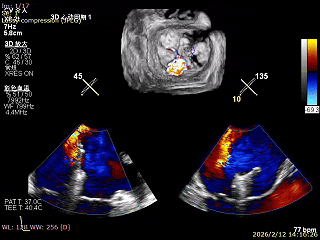

三尖瓣术前评估

三尖瓣反流(重度);肺动脉高压(中度);二尖瓣反流(中度);双房左室增大;左室顺应性减低。

术前食道超声评估

三尖瓣关闭不全重度(4+,平均缩流颈10mm),反流口以前隔、中央为主,部分后隔,瓣叶未见明显脱垂及GAP,三尖瓣环扩张(瓣环平均径43mm),二尖瓣中-重度反流,肺动脉高压(PASP:44mmHg)。

手术效果评估

反流评估:术前4+下降至1+

术前中央反流

术后中央反流

DSA双夹释放后形态无异常,锚定部位均在预期位置,RCA血流未受到影响。

术前瓣环面积

术后瓣环面积

后复查经胸心脏超声,示肺静脉、肝静脉逆流消失,二尖瓣及三尖瓣反流降低至轻度,手术效果良好。